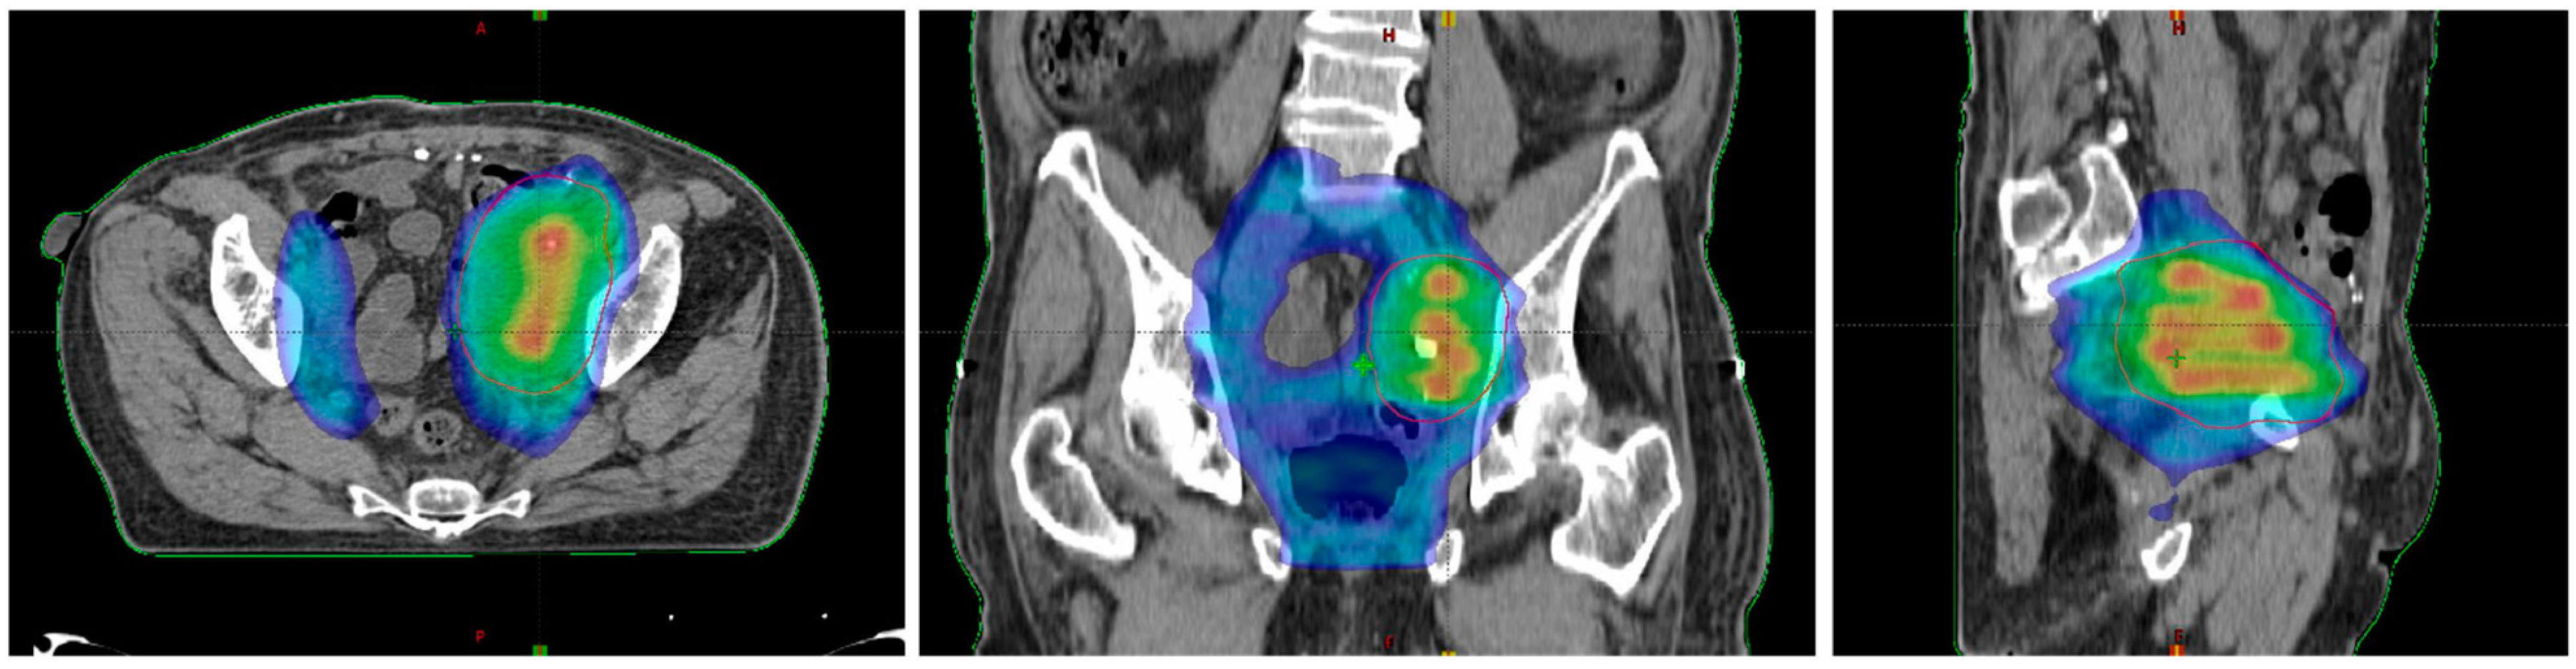

Figure 3.

Dose distribution in the axial plane (left), the coronal plane (middle), and the sagittal plane (right).